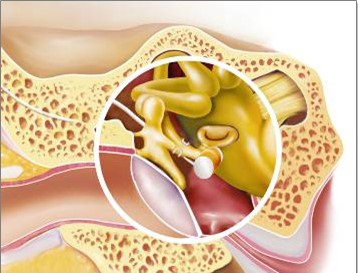

Amikor a jelenléte és FMT teljes ossicular lánc van szerelve a hosszú lábát az üllő segítségével titán klip. FMT kell közel, és párhuzamos a kengyel (5. ábra).

5. ábra - a helyét a FMT jelenlétében egy teljes lánc hallási ossicles